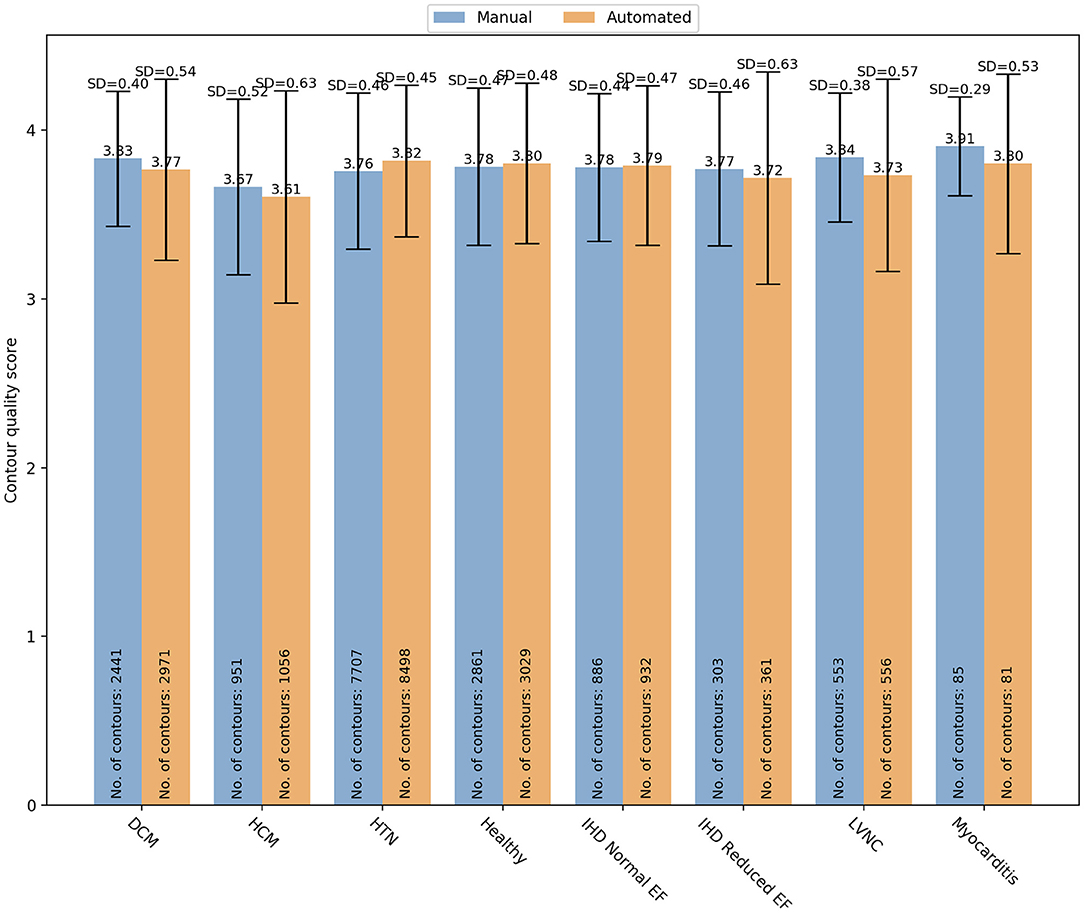

Finally, specific changes in cardiac structures associated with some conditions might also affect the contours quality. Therefore, we analyzed whether there was a variation in manual and automated quality scores based on the underlying pathology (Figure 7). In particular, we analyzed the quality score assigned for both manual and automated contours in the following subsets: DCM (manual: 3.83 ± 0.04 vs automated: 3.77 ± 0.54; OR (95% CI) = 0.59 (0.45–0.77); p < 0.0001), HCM (3.67 ± 0.52 vs 3.61 ± 0.63; OR(95% CI) = 0.83 (0.60–1.15); p = 0.27), HTN (3.76 ± 0.46 vs 3.82 ± 0.45; OR (95% CI) = 2.73 (2.22–3.37); p < 0.0001), healthy controls (3.78 ± 0.47 vs 3.80 ± 0.48; OR(95% CI) = 0.61 (0.36–1.00); p=0.051), IHD with normal (3.78 ± 0.44 vs 3.79 ± 0.47; OR(95% CI) = 1.44 (0.95–2.20); p=0.09) and reduced ejection fraction (EF) (3.77 ± 0.46 vs 3.72 ± 0.63; OR(95% CI_=0.72 (0.40–1.28); p = 0.26), LVNC (3.84 ± 0.38 vs 3.73 ± 0.57; OR(95% CI) = 0.67 (0.40–1.12); p = 0.13), myocarditis (3.91 ± 0.29 vs 3.80 ± 0.53; OR(95% CI)= 6.77 (0.70–65.43); p = 0.10). Only in DCM and HTN subgroups, there were significant differences in quality between the two contouring methods. In particular, manual contours received higher quality scores than the automated ones in DCM, while an opposite trend was observed for HTN.

Figure 7. Distribution of the overall contour quality scores by different pathologies for manual (blue) and automated (orange) segmentation. DCM, dilated cardiomyopathy; HCM, hypertrophic cardiomyopathy; HTN, hypertension; IHD, ischaemic heart disease; EF, ejection fraction; LVNC, left ventricle non-compaction.